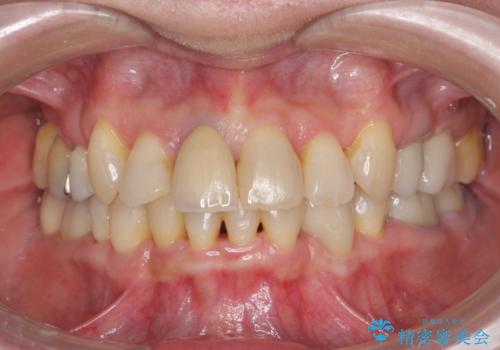

[マウスピース矯正] 海外留学中でも可能な矯正治療

担当医 大元洋佑

![[マウスピース矯正] 海外留学中でも可能な矯正治療の症例 治療前](https://seimitsushinbi.jp/wp/wp-content/uploads/2025/01/C4-1-500x350.jpg?v=1737343006)

![[マウスピース矯正] 海外留学中でも可能な矯正治療の症例 治療後](https://seimitsushinbi.jp/wp/wp-content/uploads/2025/01/IMG_0074-500x350.jpg?v=1737343049)